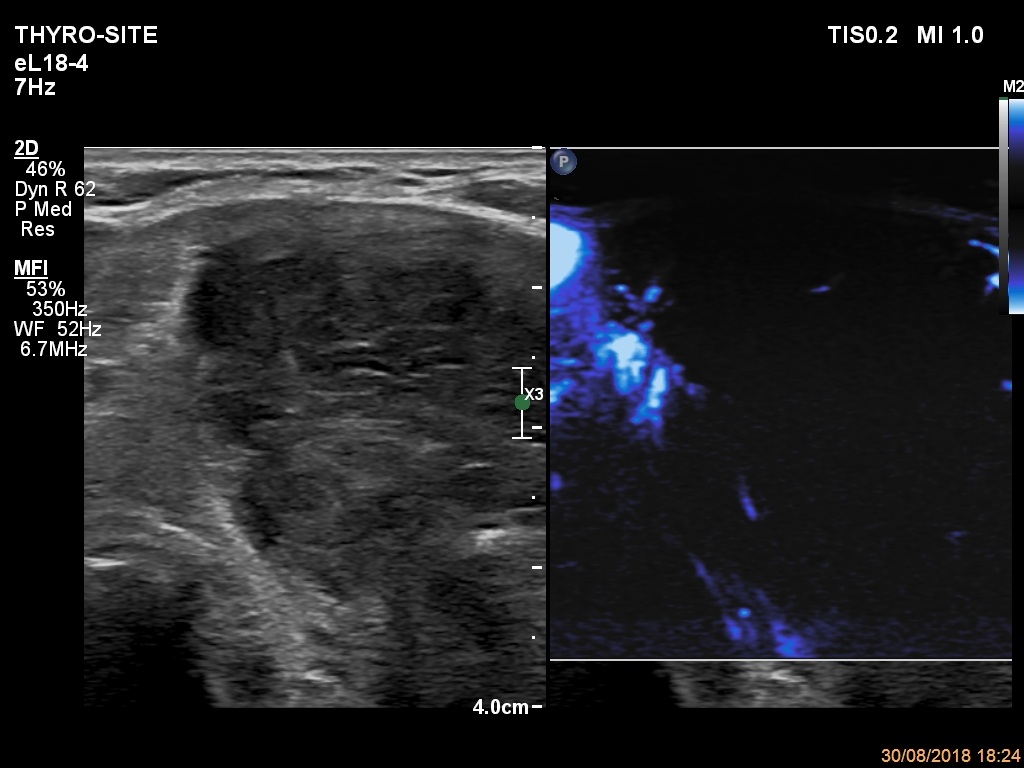

Ultrasonography. The thyroid was echonormal. There were a few hypoechogenic areas in the right lobe. There was a hypoechogenic mass with irregular shape in the left lobe. The lesion had echonormal fields and connective tissue. The microflow imaging revealed no intranodular vascularization while the lesion proved to be very hard on elastography.